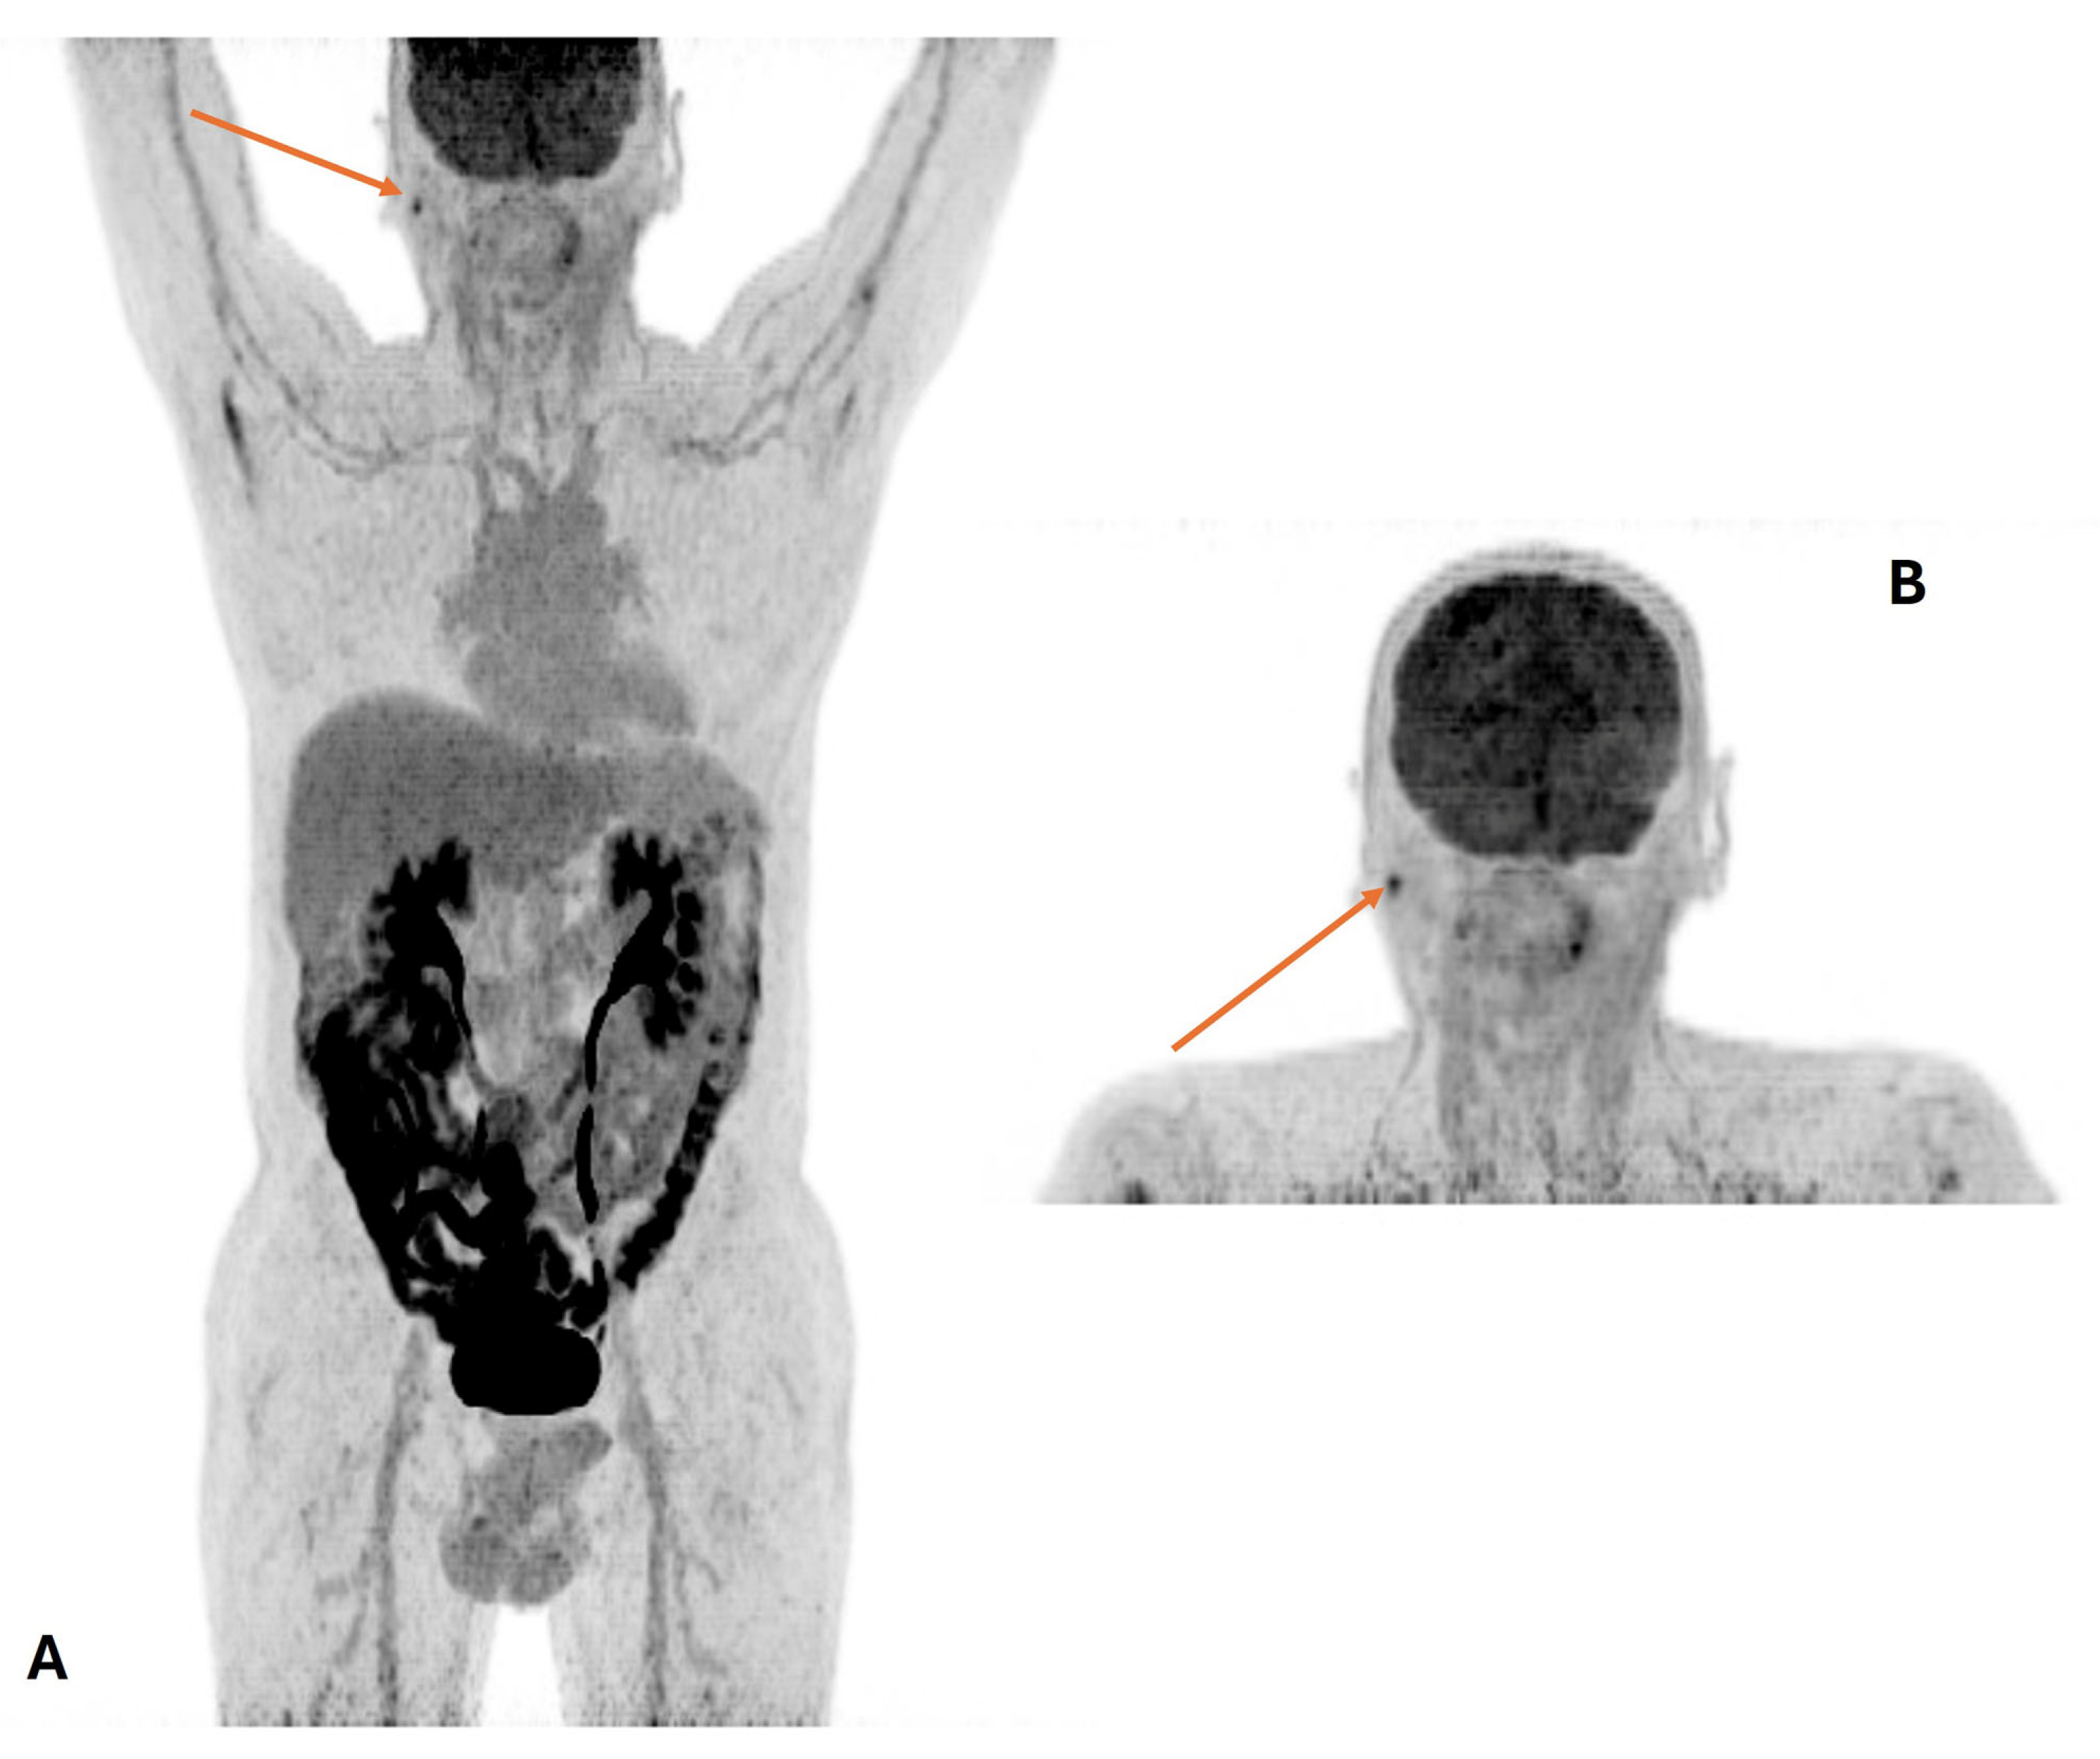

5. Treatment-Response Assessment

- Helsen, N.; Van den Wyngaert, T.; Carp, L.; De Bree, R.; VanderVeken, O.M.; De Geeter, F.; Maes, A.; Cambier, J.P.; Spaepen, K.; Martens, M.; et al. Quantification of 18F-fluorodeoxyglucose uptake to detect residual nodal disease in locally advanced head and neck squamous cell carcinoma after chemoradiotherapy: Results from the ECLYPS study. Eur. J. Nucl. Med. Mol. Imaging 2020, 47, 1075–1082. [Google Scholar] [CrossRef]

- Cheung, P.K.; Chin, R.Y.; Eslick, G.D. Detecting Residual/Recurrent Head Neck Squamous Cell Carcinomas Using PET or PET/CT: Systematic Review and Meta-analysis. Otolaryngol. Head Neck Surg. 2016, 154, 421–432. [Google Scholar] [CrossRef]

- Bar-Ad, V.; Mishra, M.; Ohri, N.; Intenzo, C. Positron emission tomography for neck evaluation following definitive treatment with chemoradiotherapy for locoregionally advanced head and neck squamous cell carcinoma. Rev. Recent Clin. Trials 2012, 7, 36–41. [Google Scholar] [CrossRef]

- Castaldi, P.; Rufini, V.; Bussu, F.; Miccichè, F.; Dinapoli, N.; Autorino, R.; Lago, M.; De Corso, E.; Almadori, G.; Galli, J.; et al. Can “early” and “late” 18F-FDG PET-CT be used as prognostic factors for the clinical outcome of patients with locally advanced head and neck cancer treated with radio-chemotherapy? Radiother. Oncol. 2012, 103, 63–68. [Google Scholar] [CrossRef] [PubMed]

- Marcus, C.; Ciarallo, A.; Tahari, A.K.; Mena, E.; Koch, W.; Wahl, R.L.; Kiess, A.P.; Kang, H.; Subramaniam, R.M. Head and neck PET/CT: Therapy response interpretation criteria (Hopkins Criteria)-interreader reliability, accuracy, and survival outcomes. J. Nucl. Med. 2014, 55, 1411–1416. [Google Scholar] [CrossRef]

- Aiken, A.H.; Farley, A.; Baugnon, K.L.; Corey, A.; El-Deiry, M.; Duszak, R.; Beitler, J.; Hudgins, P.A. Implementation of a Novel Surveillance Template for Head and Neck Cancer: Neck Imaging Reporting and Data System (NI-RADS). J. Am. Coll. Radiol. 2016, 13, 743–746. [Google Scholar] [CrossRef]

- Zhong, J.; Sundersingh, M.; Dyker, K.; Currie, S.; Vaidyanathan, S.; Prestwich, R.; Scarsbrook, A. Post-treatment FDG PET-CT in head and neck carcinoma: Comparative analysis of 4 qualitative interpretative criteria in a large patient cohort. Sci. Rep. 2020, 10, 4086. [Google Scholar] [CrossRef]

- Garibaldi, C.; Ronchi, S.; Cremonesi, M.; Gilardi, L.; Travaini, L.; Ferrari, M.; Alterio, D.; Kaanders, J.H.A.M.; Ciardo, D.; Orecchia, R.; et al. Interim 18F-FDG PET/CT During Chemoradiation Therapy in the Management of Head and Neck Cancer Patients: A Systematic Review. Int. J. Radiat. Oncol. Biol. Phys. 2017, 98, 555–573. [Google Scholar] [CrossRef]

- Hentschel, M.; Appold, S.; Schreiber, A.; Abolmaali, N.; Abramyuk, A.; Dörr, W.; Kotzerke, J.; Baumann, M.; Zöphel, K. Early FDG PET at 10 or 20 Gy under chemoradiotherapy is prognostic for locoregional control and overall survival in patients with head and neck cancer. Eur. J. Nucl. Med. Mol. Imaging 2011, 38, 1203–1211. [Google Scholar] [CrossRef]

- Chen, S.W.M.; Hsieh, T.C.; Yen, K.Y.; Yang, S.N.; Wang, Y.C.; Chien, C.R.; Liang, J.A.; Kao, C.H. Interim FDG PET/CT for predicting the outcome in patients with head and neck cancer. Laryngoscope 2014, 124, 2732–2738. [Google Scholar] [CrossRef]